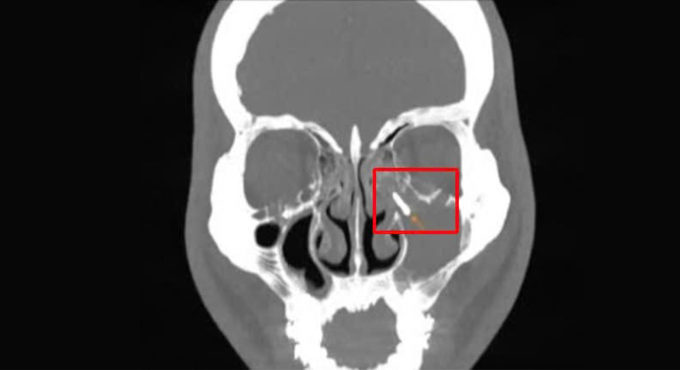

Kết quả cho thấy tổn thương lấp đầy xoang hàm trái, xơ đặc thành xoang, tắc lỗ thông xoang, có dị vật kim loại bên trong xoang. Đồng thời, các chân răng 15, 16, 17 lồi sát vào xoang hàm, dày nhẹ niêm mạc xoang hàm.

Sau khi hút sạch dịch mủ, loại bỏ mô viêm, bác sĩ thấy dị vật kim loại nằm trong lòng xoang hàm, dùng dụng cụ vi phẫu gắp trọn qua đường mũi, không làm tổn thương niêm mạc xung quanh, không chảy máu. Dị vật là một vít niềng răng khoảng 2 cm. Êkíp kiểm tra lại lòng xoang, đảm bảo không còn dị vật, làm sạch xoang, ngăn tái phát viêm.